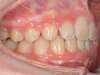

Cas 5 : Description

Absence congénitale des incisives latérales supérieures. Appareils fixes pour créer l’espace nécessaire à la mise en place de facettes en remplacement des latérales.

Après